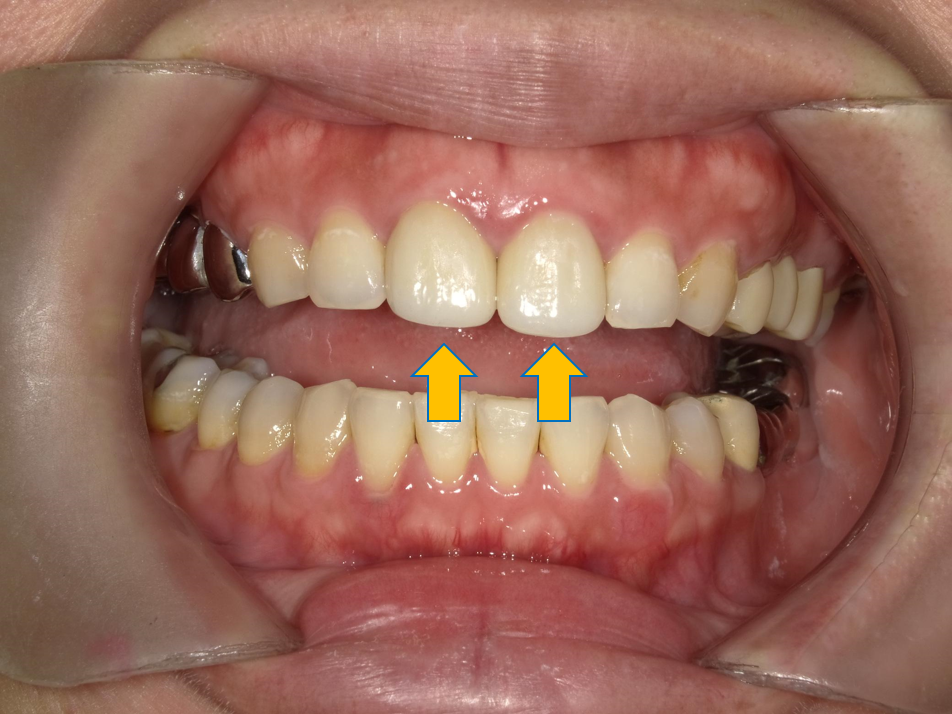

案例 2 術後(After)

門牙重建,改善牙縫過大問題